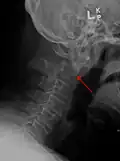

A fracture of the base of the dens as seen on plain X-ray -

A fracture of the base of the dens as seen on CT -